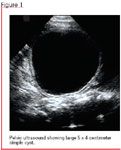

You refer the child to urology for evaluation of her hydronephrosis. The pediatric urologist orders a US, which continues to demonstrate mild bilateral hydronephrosis, improved from her prenatal US. However, a nearly 4-cm cyst is also noted in the pelvis near the bladder. (The antenatal US was done at a small outlying community hospital. The radiologist's report noted the hydronephrosis; there was no comment about a cyst antenatally.)

In a female infant of this age, you know a cystic mass in the pelvis is unusual, but very likely an ovarian cyst. The most common cause of a pelvic mass in a female is an ovarian cyst, but generally speaking, the most common cause of abdominal (including flank) mass would be multicystic dysplastic kidney (MCDK). Smaller ovarian cysts will typically disappear by six to nine months of age. However, you also know that larger ovarian cysts need to be closely followed, as they may not spontaneously involute and even have the risk of acute torsion. Finally, you question if this cyst could be something else, such as a mesenteric cyst, duplication cyst, or giant Meckel's diverticulum, as the radiologist cannot fully see the cyst arising from the adnexa.